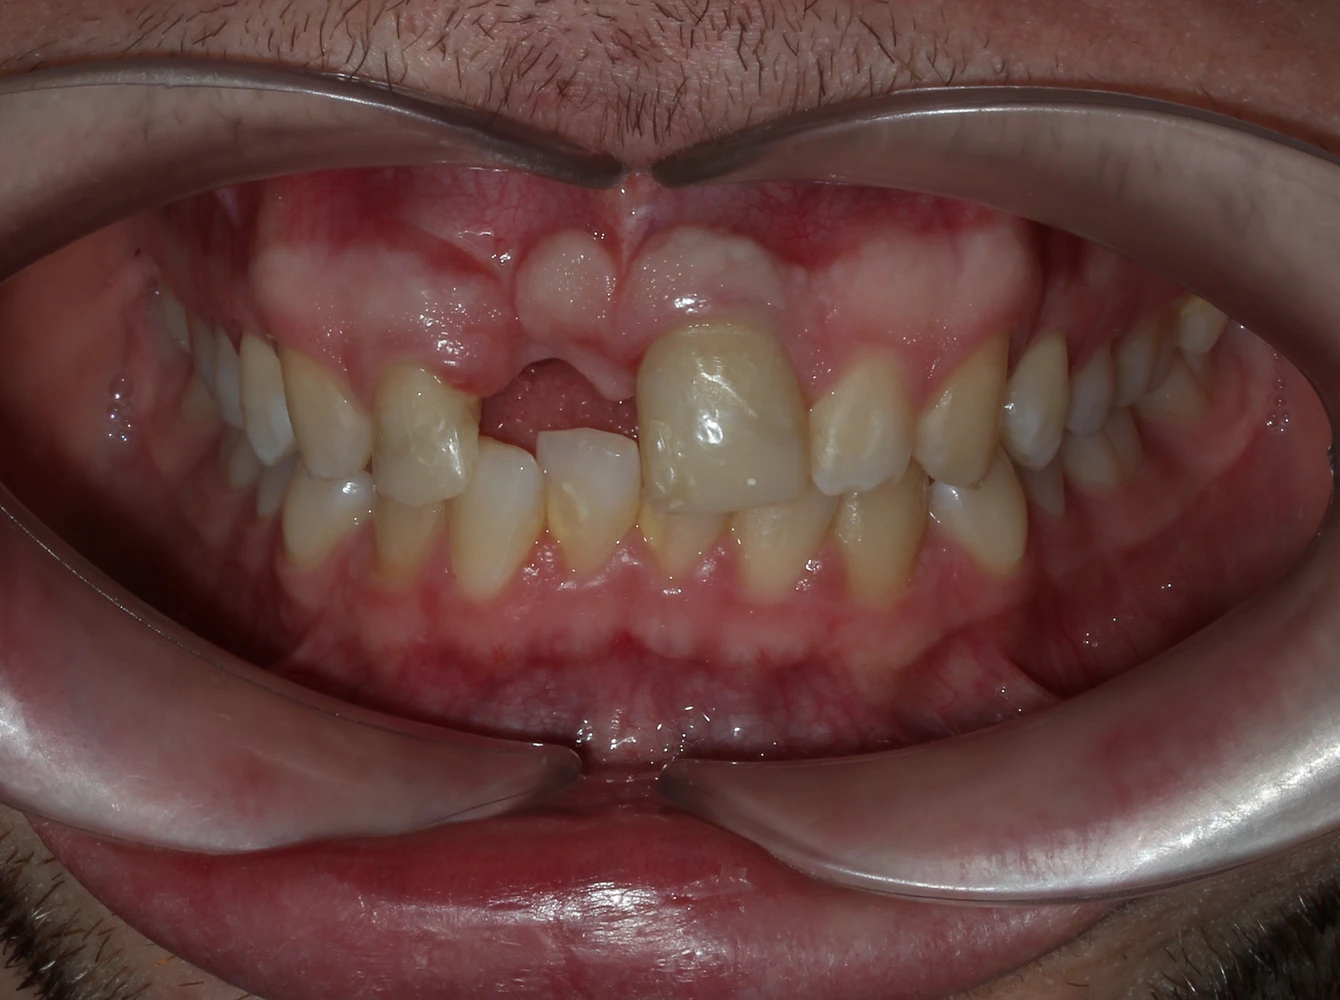

Diagnosticul inițial

Pierderea incisivului frontal

Traumatism dentar cu avulsia completă a dintelui 21

Defect osos alveolar

Resorbție osoasă moderată în zona edentată

Impact estetic și funcțional

Dificultăți fonetice și disconfort estetic marcat

Alexei, un tânăr energic și activ, a suferit un accident în timpul unei vacanțe cu prietenii, în urma căruia a pierdut un incisiv superior central. Pe lângă impactul estetic major, trauma a dus și la pierdere de volum osos și gingival în zona afectată, ceea ce a făcut necesară o reabilitare implanto-protetică complexă.